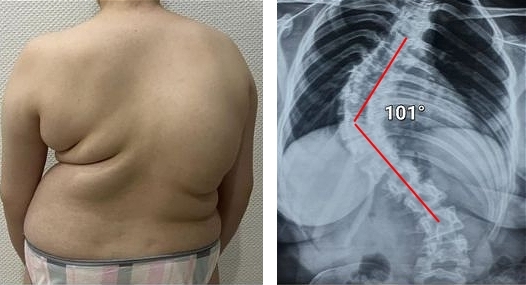

Lihat foto-foto ini. Inilah yang terjadi pada mereka yang tidak memperhatikan gejala. Hari ini, mereka adalah orang-orang yang tak berdaya, dan banyak di antara mereka tidak memiliki siapa pun untuk membantu. Apakah Anda menginginkan nasib seperti itu?

Wanita, 52 tahun. Pergeseran parah dan deformasi cakram tulang belakang dengan kompresi saraf serta kerusakan sumsum tulang belakang.

"Punggung bungkuk janda" — deformasi tulang belakang yang menyebabkan nyeri tak tertahankan yang semakin memburuk setiap hari.